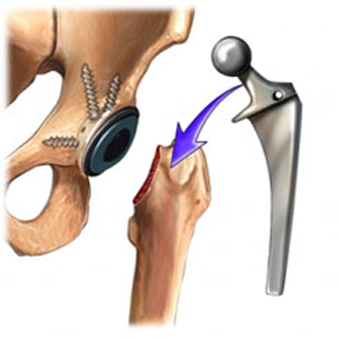

Hip Replacement

Hip replacement surgery also known as hip arthroplasty, is a surgery involving the removal of diseased or damaged parts of hip joints, and then replacing them with an artifical one. These artifical parts called the prosthesis, are made of metals or high density plastics. Hip replacement surgery is recommended for patients suffering from pain due to damaged hip joint.Depending upon the condition of the hips, the surgery can be performed in two ways, as a total hip replacement or a hemi hip replacement surgery.